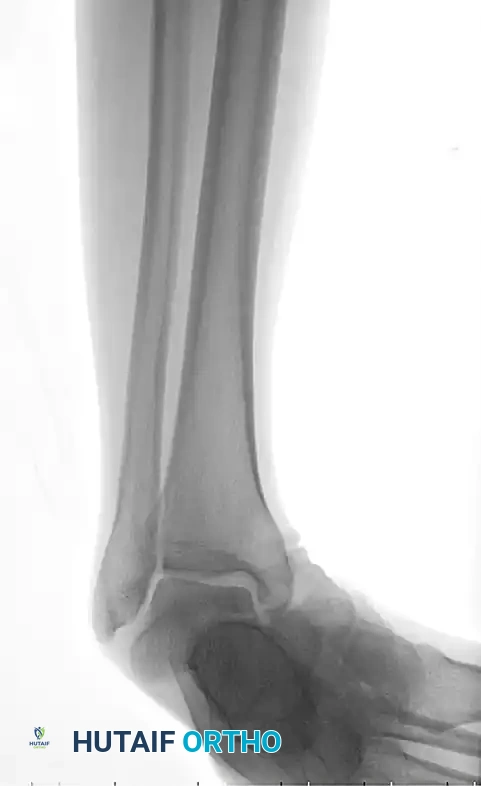

Standard trauma radiographs of the ankle (AP, lateral, and mortise) and foot (AP, lateral, and oblique) are required.

Radiographic appearance of a medial subtalar dislocation. The talonavicular and talocalcaneal joints are completely disrupted.

Radiographs demonstrating a lateral subtalar dislocation before and after reduction.